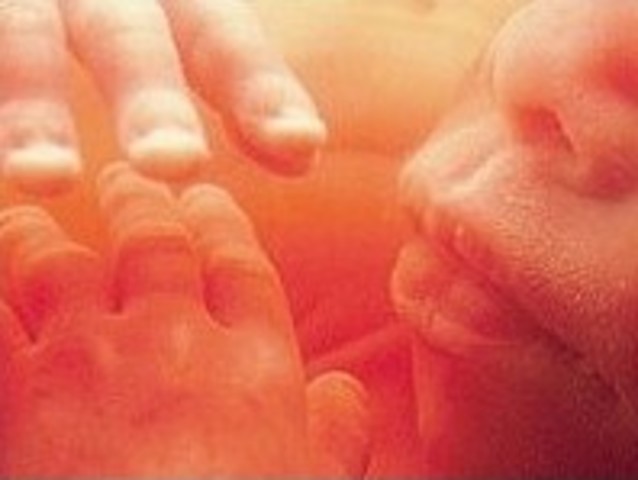

• Week 12 of the First Trimester

Week 12 of the First Trimester

The Fetus has developed alot, it now has the ability to feel pain and cry. A scan of the female's stomach can reveal how active the Fetus is.

Facts:

1)The fetus is now about 2.5 inches (6cm) length and weighs about 0.7 ounce (20 g).

2)Fingernails and toenails appear.